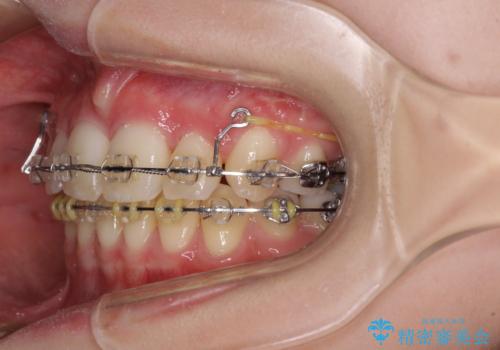

治療途中で転院 抜歯矯正の仕上げ治療

- 地元で抜歯治療を行っている途中、東京へ転職したため治療を継続して欲しいとのことで来院された患者様です。

出っ歯を抜歯矯正にて治療をしていらっしゃいましたが、抜歯スペースが少し残っていたため、閉じて歯列を仕上げていくこととしました。